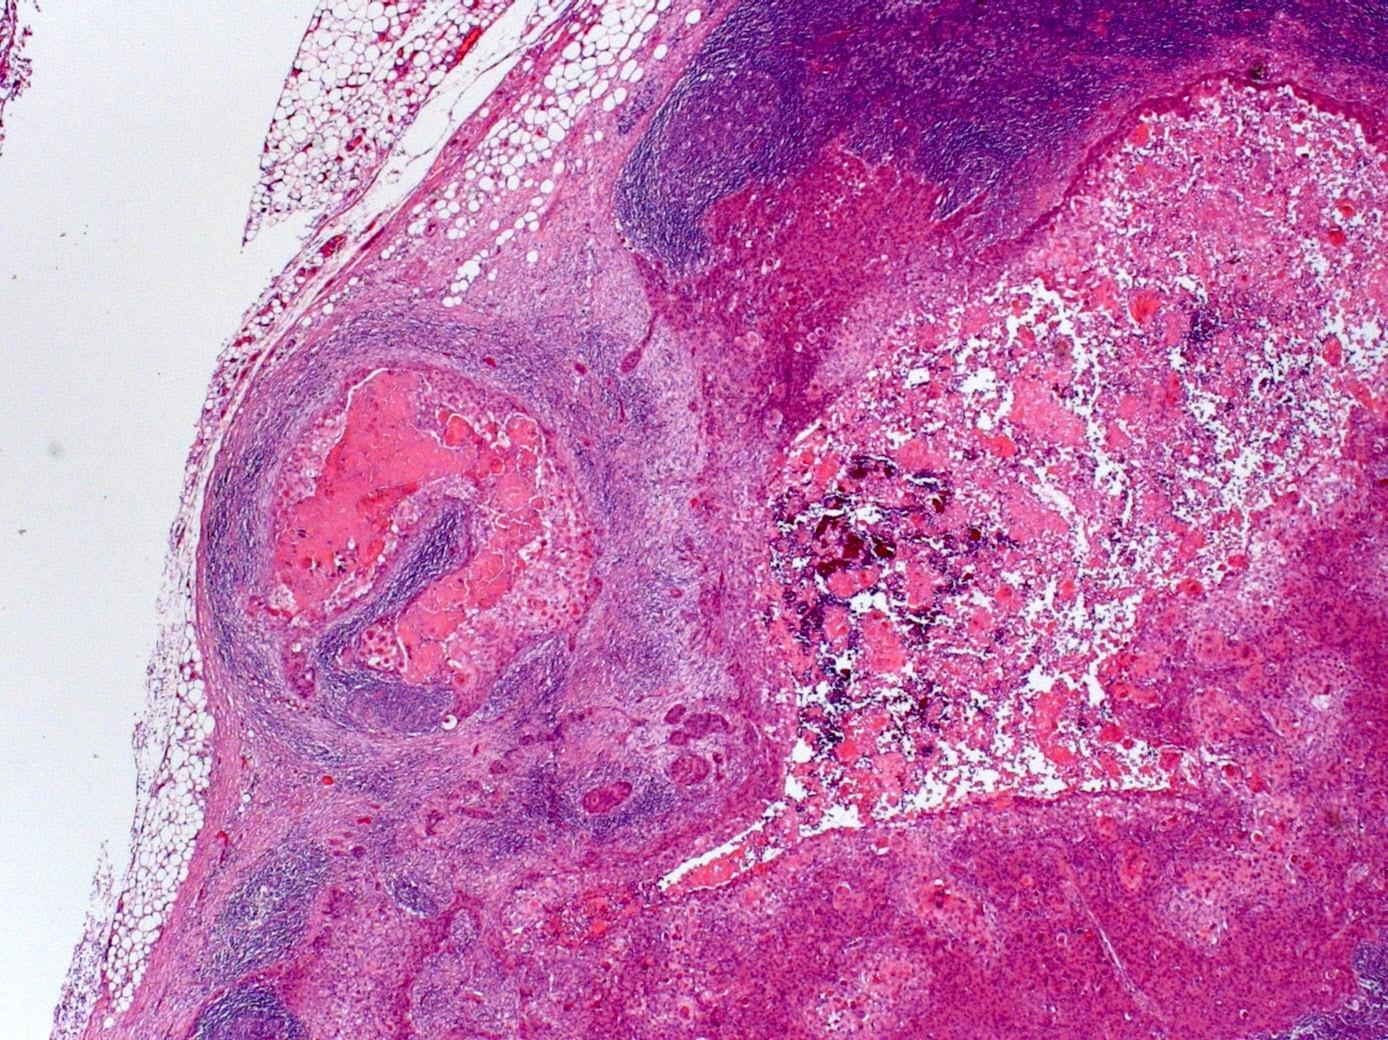

Microscopic ECS

Macroscopic ECS

Macro ECS – nerves and vessels

Importance of microscopic ECS